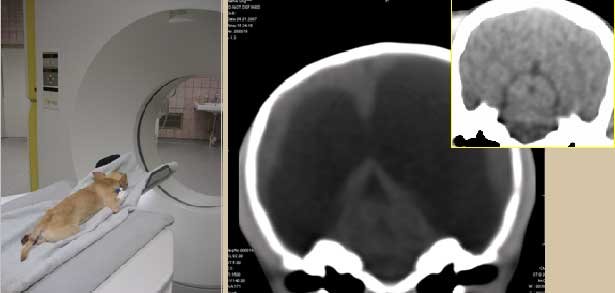

Компьютерная томография. Увеличение боковых мозговых желудочков у собаки с гидроцефалией (очаги просветления в виде «темных пятен»). Сегментальный срез. В норме боковые мозговые желудочки визуализируются на томограмме в виде узких щелеобразных просветлений.